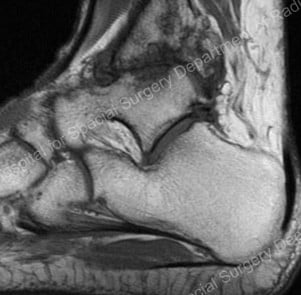

To understand how the procedure works you must first have a little knowledge about arthritis. Arthritis is the loss of articular cartilage (the smooth surface that covers the ends of our bones in our joints) from the joint surfaces. This is often seen as a loss of joint space on X-ray and MRI (Figure 3).

Figure 3: loss of joint space (upper center of image)